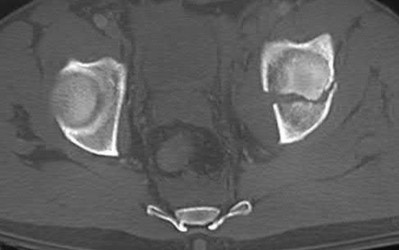

Which of the following images shows an injury pattern most consistent with a lateral compression type 3 pelvic ring injury?

Figure C is an axial CT scan of a lateral compression type 3 (LC3) pelvic ring injury.

Classically, LC3 injuries demonstrate an ipsilateral lateral compression and a contralateral APC (windswept pelvis) fracture pattern. The most common mechanism of injury in these cases is a rollover MVC or pedestrian vs. auto. LC1 injuries are characterized by an oblique or transverse ramus fracture and ipsilateral anterior sacral ala compression fracture, while LC2 injuries consist of a rami fracture and ipsilateral posterior ilium fracture dislocation (crescent fracture). While LC1 injuries can often initially be managed conservatively with protected weight-bearing and close observation, LC2 and LC3 pelvic ring injuries are almost universally operative.

Pennal et al. discuss a radiologic technique for assessing the forces producing pelvic disruption and its use in logically classifying pelvic injury. Based on this radiologic assessment and along with some biomechanical studies, they propose a classification system involving three major forces producing injury that can also be helpful in the management of these patients.

Young et al. performed a retrospective analysis of the plain radiographs of 142 cases of pelvic fractures and identified four patterns of force that presented with distinctive, recognizable radiographic appearances. They describe a classification system for pelvic fractures based on radiographic and clinical findings that correlates with associated injury to soft-tissue structures and enables the surgeon to begin corrective procedures rapidly.

Incorrect Answers:

Answer 1: This represents a lateral compression type 2 injury. Answer 2: This represents a lateral compression type 1 injury.

Answer 4: This represents an anterior posterior compression type 2 injury. Answer 5: This represents an anterior posterior compression type 3 injury.